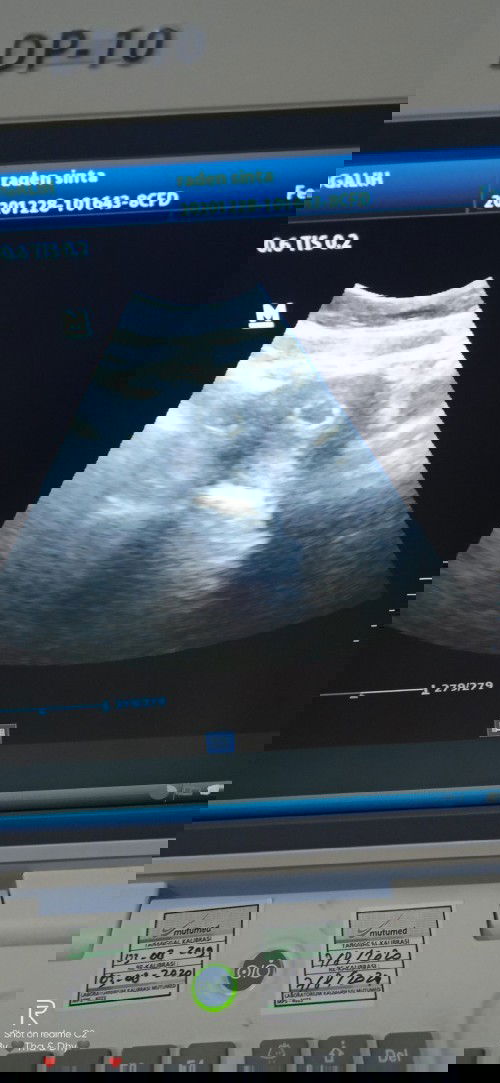

Hamil 8 Minggu masih berupa kantung

Maaf bunda mau bertanya .. Saya hamil sudah 8 Minggu dan sempat keluar flek.. Lalu saya USG .. kata dokter masih berupa kantung .. besok saya ada jdwal buat kontrol lagi.. Kira" ini gmn ya bund?? Bagi pengalaman nya buat yg pernah mengalami 🙏 Terimakasih